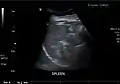

Spleen seen on abdominal ultrasonography

Maximum length of spleen on abdominal ultrasonography